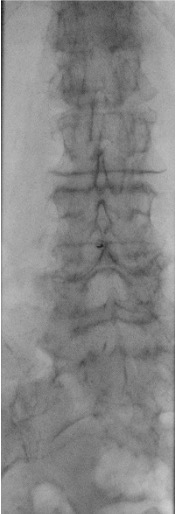

The conus medullaris typically terminates at the L1 vertebral level in adults (range L1–L2). Target the L2–L3 or L3–L4 interspace to remain safely below the conus and in the cauda equina region. The L4–L5 interspace is an acceptable alternative. The iliac crest approximates L4 on the lateral fluoroscopic view.

Fluoroscopic Views

When bedside US-guided or blind LP fails, fluoroscopy (prone or lateral decubitus) provides definitive guidance. The PA view confirms midline needle position; the prone oblique view opens the interspace and aligns the X-ray beam parallel to the disc for optimal interlaminar access.

- Fluoroscopic survey: identify target interspace (L2–L3 or L3–L4), confirm midline, assess interspace width